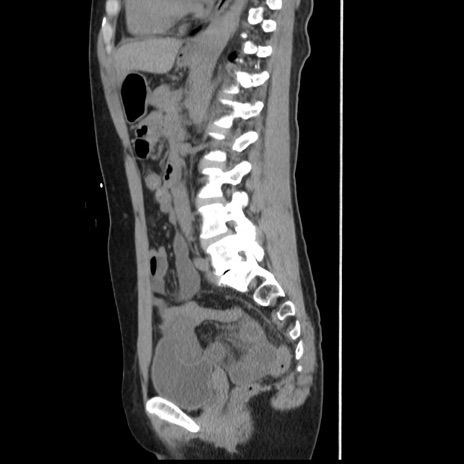

症例10(矢状断像)

【症例】 50歳代女性

【主訴】 腹痛

【現病歴】前日生レバーを食べた。今朝に排便あり。 昼前に突然発症の腹痛を生じ、当院救急外来を受診した。

【既往歴】 子宮筋腫にてで子宮全摘後

【身体所見】 意識清明、腹部:平坦、軟、下腹部やや左を中心に圧痛・反跳痛あり、筋性防御あり

【データ】WBC 7800、CRP 0.07